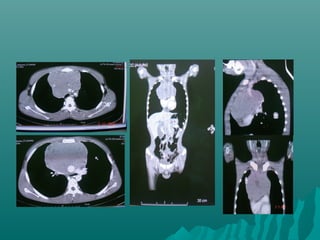

TEM EN TORAXTEM EN TORAX

Indicaciones para examen deIndicaciones para examen de

toraxtorax

Modo en espiral para estudios de rutina deModo en espiral para estudios de rutina de

torax v.g.torax v.g.

Neumonia, tumores, metástasis , linfomaNeumonia, tumores, metástasis , linfoma

anormalidades vasculares entre otrosanormalidades vasculares entre otros